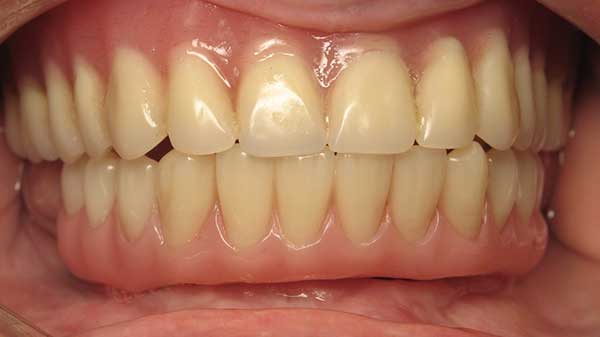

Anthony A.

This patient had only a few remaining infected teeth, but didn’t want to settle for just a denture.  Placed multiple implants and provided a secure fixed option which allowed him to not only chew better but to smile again.